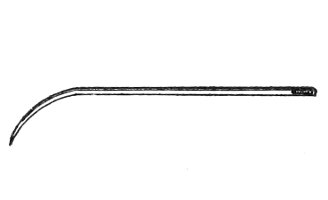

The uterine sound is an instrument by which the length of the uterine cavity may be determined (Fig. 15). The sound, which is a large surgical probe, somewhat curved to adapt itself to the normal shape of the uterine axis, is made of pliable metal, so that the curvature may be changed readily to suit any case. The sound is graduated, and at a position of 2½ inches from the tip is a small elevation marking the length of the normal uterine cavity.

Fig. 15.—Uterine sound.

The uterine sound was at one time used a great deal to determine the length and direction of the uterus, and 35 perhaps to assist in determining the character of the uterine contents or of the endometrium. With our present methods of examination, however, the sound is of but little if any use. The size and direction of the uterus can in nearly all cases be determined by bimanual examination. The use of the uterine sound is by no means free from danger. Many cases of septic endometritis and salpingitis have been caused by it, and the physician has often unintentionally committed an abortion by passing the sound in a pregnant woman. The uterine sound should never be used in a routine way. It should never be used unless one expects to determine with it something that cannot be determined by simpler methods of examination.

The most thorough aseptic precautions should be observed when the sound is introduced. The vulva, vagina, and cervix should be cleaned and the sound should be sterilized. The sound should never be introduced if there is any suspicion of pregnancy.